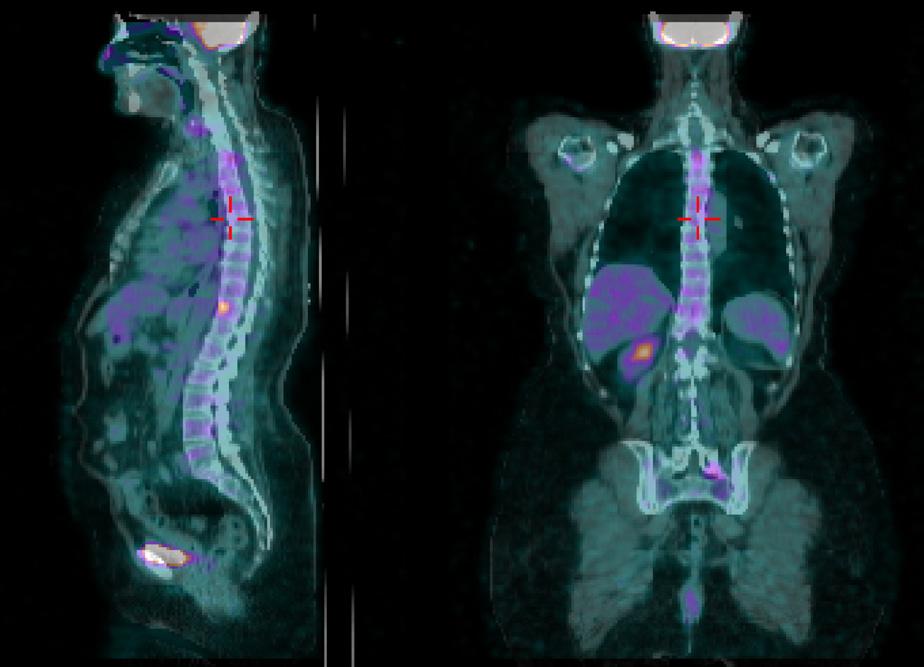

Alla PET di Novembre 2021 (figura 4) si evidenzia ulteriore PD scheletrica su D9 e osso sacro per cui dal 17/12/2021 al 04/01/2022 è stata sottoposta a trattamento RT i salvataggio su (D9- Sacro ) con tecnica 30 Gy. La paziente prosegue con il doppio blocco fino al mese di Luglio 2022 (56° ciclo di pertuzumab e trastuzumab).

In seguito ad ulteriore progressione scheletrica riscontrata nel mese di Agosto 2022 (figura 5) la paziente ha pertanto avviato una seconda linea di trattamento con T-DXd 5,3 mg/kg nell’ambito del programma a uso nominale, ottenendo una risposta completa di malattia alla PET di Novembre 2022 (figura 6) dopo soli 3 cicli di trattamento. Dal 02/01/2023 prosegue a terapia ridotta al I livello 4,4 mg/kg per quadro di tossicità gastrointestinale con nausea G2, vomito, diarrea G2 e inappetenza. Dal secondo ciclo abbiamo potenziato la premedicazione antiemetica con desametasone per os per 3 giorni. Nonostante ciò la paziente ha riportato nausea G2 per i primi sette giorni dopo l’infusione e nausea G1 per i successivi 14 giorni. Da quando abbiamo ridotto la dose al I livello la paziente non lamenta alcun disturbo, in questo modo c’è stato un miglioramento dei sintomi, con conseguente prosecuzione della terapia con T-DXd senza interruzioni e con una ottima qualità della vita. Ottobre 2023 riscontro clinico di fini crepitii alle basi polmonari bilateralmente, no aree di ottusità alla percussione, parametri vitali nella norma. Si esegue HRTC, visita cardiologica con ecocardio e valutazione della FEVs ed indici di flogosi PCR e procalcitonina per escludere eziologia infettiva. La paziente nega disturbi, porta in visione gli indici di flogosi e visita cardiologica che risultano nella norma, la HRTC (figura 7) rileva la comparsa di ispessimenti interstiziali subpleurici bilateralmente; coesistono alterazioni a vetro smerigliato. La strategia intrapresa è stata quella di interrompere il trattamento con T-DXd ed iniziare una terapia con prednisolone 1 mg/kg per 20 giorni con graduale riduzione della dose e ripetizione della HRTC